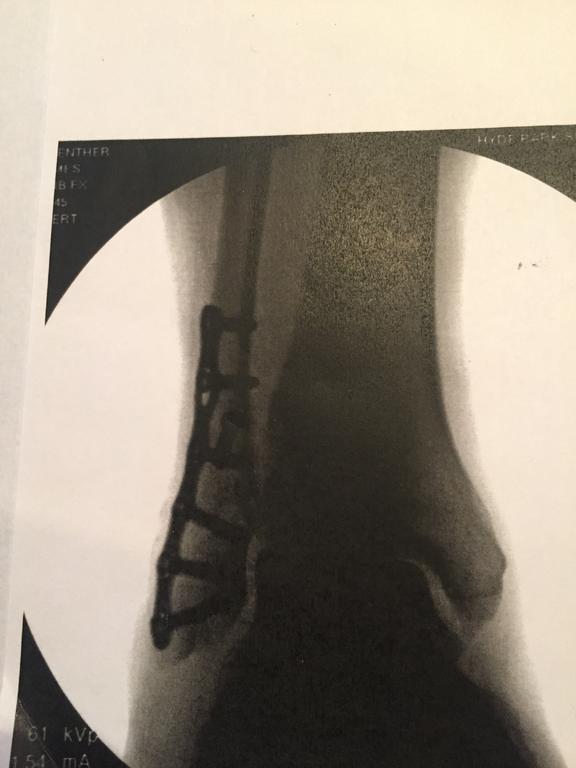

oliver2-44 11,424 #1 Posted April 9, 2018 Everyone ask me "what's the story". But I don't have a good one to tell.: i went out to the shop after Supper to work on a carb cleaning and valve adjustment on my 1974 C-160. Made good progress and about 9pm I wrapped up and headed for the house. Moments later I found myself tripping over the patio recliner, doing some aerobatics and landing flat on the concrete. I had went to the shop before dark so I had not turned the patio lights on. Now, It was a dark night and the solar lights that should have been lighting the patio walkway were dead since they were over a year old. For the next 3 days I limped at work thinking my right foot was just bruised. Seeing the swelling was not going down I went to my Family Physician. He ran his hand across my ankle/lower leg and imeciately said it was broken. X-rays and a visit to a Orthopedic Foot Specialist confirmed surgery was needed. In the 1st photo below you can see the plate and six screws. that clamp the candy cane spiral break back together. In the 2nd photo you can just make out the long angled screw that pulls my small leg bone down tight toward the ankle. Surgery was last Thursday and mildly painful for a few days. Now, Im doing better, My wonderful wife is taking excellent care of me (although she had already said I wont be slipping out to the shop with my crutches) and the good lord is always with me. Lots of couch time and learning to walk on crutches. I will be off work at least 4 weeks and on crutches up to 8 weeks. This is my 1st broken bone in my 61 years. Hard to grasp that I did it by tripping where I walk every day 1 2 Share this post Link to post Share on other sites